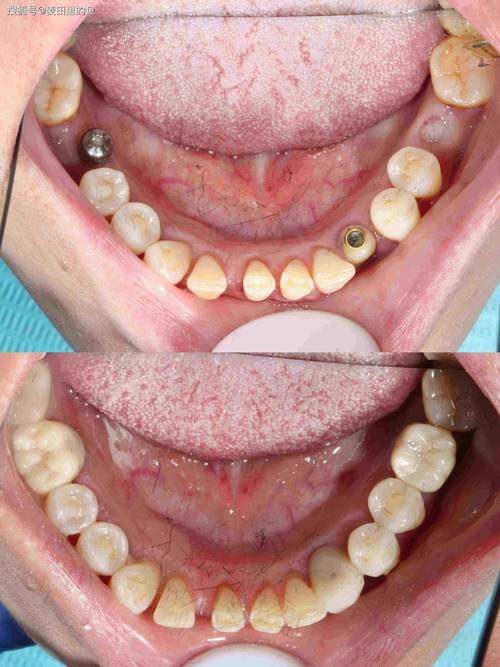

种植牙作为一种理想的牙齿修复方式,通过将人工种植体植入牙槽骨内,模拟天然牙根的功能,再安装牙冠恢复牙齿形态与咀嚼能力,许多患者在完成种植体植入手术后,最关心的问题便是“多久能戴牙冠”,这一时间并非固定,而是受多种因素综合影响,需要结合个人情况由医生专业判断。

种植牙能否戴牙冠,首要前提是种植体与牙槽骨完成“骨结合”,骨结合是指种植体表面与周围骨组织之间形成直接的 structural connection,两者紧密结合,如同天然牙根与牙槽骨的关系,这一过程是种植牙稳定性和长期使用的基础,若骨结合未充分形成就过早戴牙冠,可能导致种植体松动、脱落甚至失败。

骨结合的时间受多种因素影响,通常需要3-6个月,但部分患者可能需要更长时间,骨结合的速度与牙槽骨的质量、患者的身体状况、种植体的设计等密切相关,牙槽骨条件好、骨质致密的患者,骨结合可能更快;而牙槽骨萎缩、需要进行植骨手术的患者,则需要额外等待植骨区域愈合,骨结合时间会相应延长。